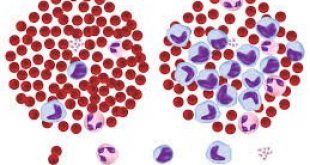

Η Περιφερική Αρτηριακή νόσος (ΠΑΝ) είναι η νόσος που χαρακτηρίζεται από μειωμένη αιμάτωση των κάτω άκρων, λόγω στένωσης ή απόφραξης των αρτηριών των κάτω άκρων. Η κύρια αιτία της ΠΑΝ των κάτω άκρων είναι η αθηροσκλήρωση, που σημαίνει σκλήρυνση των αρτηριών. Φυσιολογικά, το εσωτερικό τοίχωμα των αρτηριών σας (ενδοθήλιο) είναι ομαλό και απρόσκοπτο, με τα χρόνια όμως μπορεί να σχηματίσει μια ανώμαλη προβολή που ονομάζεται αθηρωματική πλάκα. Η πλάκα αυτή αποτελείται από χοληστερόλη, ασβέστιο και ινώδη ιστό. Στην αθηροσκλήρωση οι αρτηρίες στενεύουν ή αποφράσουν καθώς η αθηρωματική πλάκα των τοιχωμάτων τους αυξάνεται.

Οι αρτηρίες των κάτω άκρων παρέχουν στους μύες των ποδιών οξυγόνο και θρεπτικά συστατικά μέσω του αίματος. Εάν η ροή του αίματος διακοπεί, εξαιτίας της απόφραξης μίας αρτηρίας, τότε η έλλειψη οξυγόνου στην περιοχή, προκαλεί μυαλγία, ιδίως κατά την άσκηση, το περπάτημα ή όταν ο ασθενής επιχειρεί να ανέβει σκάλες. Σε αυτές τις περιπτώσεις ο ασθενής σταματάει την άσκηση ή το περπάτημα και συνεχίζει ξανά μετά από λίγα λεπτά ξεκούρασης. Τα αιμοφόρα αγγεία με την πάροδο του χρόνου συνεχίζουν να στενεύουν και κάποια στιγμή αποφράσσονται εντελώς. Όταν συμβεί απόφραξη μίας ή περισσότερων αρτηριών του κάτω άκρου, τότε η ροή του αίματος στο πόδι μειώνεται σημαντικά και η έλλειψη οξυγόνου απειλεί μύες και ιστούς. Η κατάσταση αυτή ονομάζεται “κρίσιμη ισχαιμία”.